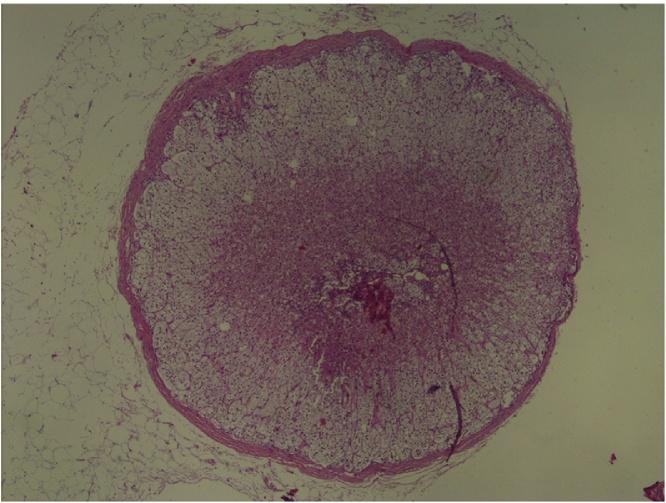

A 65-year-old patient with progressive pelvic pain and postmenopausal vaginal bleeding was evaluated by transvaginal ultrasound, which revealed bilateral adnexal masses measuring 5cm in size and a normal uterus with an increased endometrial thickness of 7mm. Initially the endometrial sampling result was reported as benign. The patient underwent abdominal hysterectomy and bilateral salpingo-oophorectomy and the pathological diagnosis was again benign, with serous ovarian cystadenoma being found in both ovaries. The pathologist also reported incidental ectopic adrenal tissue on the wall of the left ovarian cystadenoma.

一名65岁有进行性盆腔疼痛和绝经后阴道出血的患者接受经阴道超声检查,结果显示双侧附件有大小为5厘米的肿块,子宫正常,子宫内膜厚度增加至7毫米。最初子宫内膜取样结果报告为良性。患者接受了腹式子宫切除术和双侧输卵管卵巢切除术,病理诊断再次为良性,双侧卵巢均发现浆液性卵巢囊腺瘤。病理学家还报告在左侧卵巢囊腺瘤壁上偶然发现异位肾上腺组织。